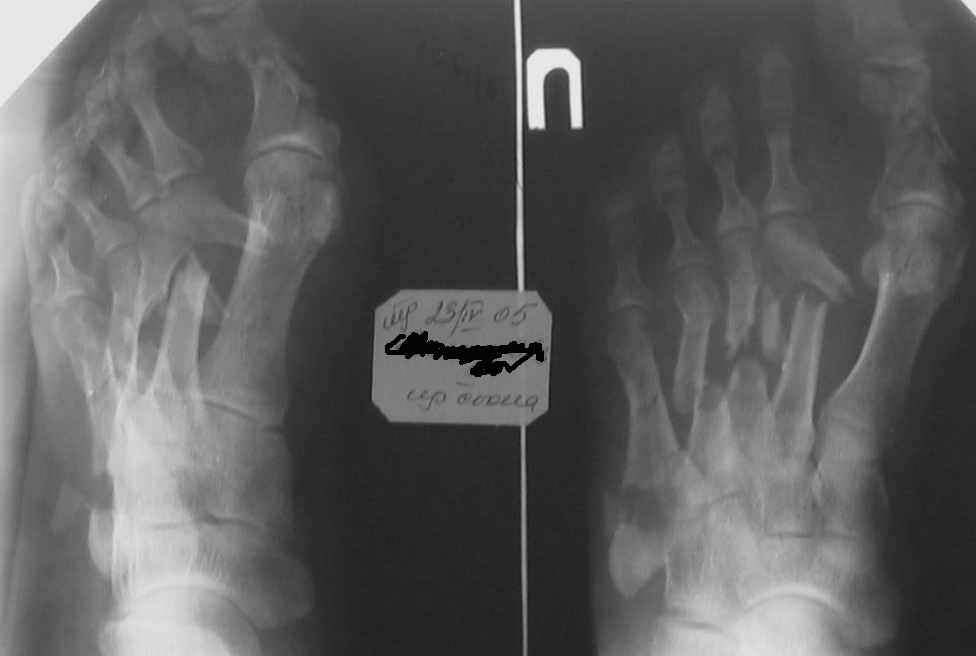

Уважаемые коллеги! Мужчина 51 год, 23 апреля 2005 года на стопу упала мет. балка. Получил открытые переломы плюсневых костей.

При поступлении ПХО, гипсовая лонгета, на следующий день множественные фликтены. Стабилизация в АВФ на третий день. В дальнейшем, по всей видимости, компартмент синдром с некрозом участка кожи на тыле стопы. Проводились этапные некрэктомии, в т. ч. дезартикуляция второго пальца. К сожалению, в силу сложившихся обстоятельств, пациент побывал в руках не единственного хирурга (не отрицаю в первую очередь своих). Дальнейшее лечение - консервативное, направленное на заживление раны. Аппарат демонтирован через 3 месяца. Сейчас ходит с небольшой нагрузкой. Прошу указать на допущенные по Вашему мнению тактические ошибки и дать советы по дальнейшему ведению больного. С уважением, А.Минервин. О себе: Минервин Алексей, заведующий травматологическим отделением ГБ 3 г. Муром, Владимирской области.

Здравствуйте, Тимур Вячеславович. ".случай действительно тяжелый, и результат по видимому будет не плохой"(?) Опечатка (не очень хороший?). Снимок самый свежий- 2-х недельной давности-тот, что самый левый в строке. Вопроса два. 1)ориентировочные сроки выполнения корригирующих операций в данном случае; 2)куда можно направить больного с учетом нашего региона (случай неординарный для лечения в районе).

Дальнейшее ведение Вашего пациента, по моему мнению, должно свестись к коррекции возникших биомеханических нарушений функции стопы, в отдельных случаях удается обойтись ортопедическими стельками или подбором специальной обуви, при условии что представленный Вами снимок не последний и положение отломков все- таки стало лучше.

Если же последний снимок с таким положением отломков, то больному в дальнейшем показана коррегирующая операция. Открытая репозиция, при необходимости остеотомии и фиксация пластинами,либо фиксация в аппарате. Любая методика должна быть направлена на восстановление свода стопы и ее амортизирующей функции.